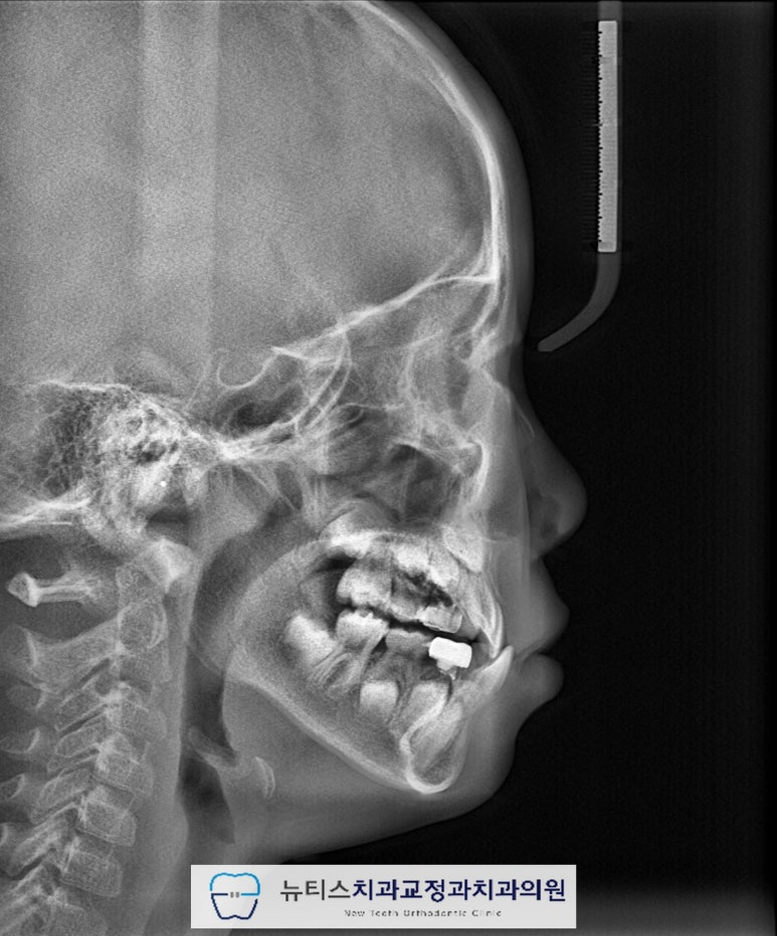

¾È³çÇϼ¼¿ä.ºÎ»ê ±ÝÁ¤±¸ ±¸¼µ¿¿¡ À§Ä¡ÇÑ´ºÆ¼½ºÄ¡°ú±³Á¤°ú Ä¡°úÀÇ¿ø±³Á¤°ú Àü¹®ÀǾȼö¹ü ¿øÀåÀÔ´Ï´Ù. À̹ø ÁÖºÎÅÍ À帶°¡ ½ÃÀ۵ȴٰí ÇÕ´Ï´Ù~Áö³ÁÖ¿¡µµ À帶°¡ ½ÃÀ۵ȴٰí ÇÏ´øµ¥...7¿ùÀº ÈÄ´þÁö±ÙÇÑ ³¯¾¾°¡ À̾îÁö³×¿ä. ÀϱⰡ º¯È¹«»óÇÏ´Ï´Ùµé °Ç° °ü¸® Àß ÇÏ½Ã±æ ¹Ù¶ø´Ï´Ù~ À̹ø¿¡ Æ÷½ºÆÃÇÒ ÄÉÀ̽º´Â"#ºÎ»ê¾î¸°À̹ݴ뱳ÇÕ ÀÔ´Ï´Ù. ¹Ý´ë±³ÇÕÀ» °¡Áö°í ÀÖÀ¸¸é Á¤»óÀûÀÎ ¼ºÀå ¹ßÀ°À» ÇÏÁö ¸øÇÏ¿©ÁÖ°ÆÅÎÀÌ ´õ ½ÉÇØÁú ¼ö ÀÖÀ¸¸ç ºÎÁ¤±³ÇÕÀÌ ¹ß»ýµË´Ï´Ù. ¼ºÀÎÀÇ °æ¿ì ½ÉÇÑ ¹Ý´ë±³ÇÕ Áï, ÁÖ°ÆÅÎÀº ±³Á¤Ä¡·á¸¸À¸·Î ÇØ°áÀÌ ¾î·Á¿ï ¼ö ÀÖÀ¸³ª ¼ºÀå±â ¾î¸°ÀÌÀÇ °æ¿ì¿¡´ÂÁ¤»óÀûÀÎ ¼ºÀå ¹æÇâÀ¸·Î À¯µµÇØ º¼ ¼ö ÀÖ½À´Ï´Ù. À̰¡ Ʋ¾îÁö°í µ¡´Ï°¡ Àְųª °ø°£ÀÌ ¸¹ÀÌ ÀÖ´Â °æ¿ì¿¡´Âº¸È£Àںв²¼ ÀÎÁö°¡ ºü¸£³ªÀÌ·± ºÎÁ¤±³ÇÕ (¹Ý´ë±³ÇÕ) À» °¡Áö°í ÀÖÀ¸¸é Àß ¸ð¸£½Ã´Â °æ¿ì°¡ ¸¹½À´Ï´Ù. ÈçÈ÷ ¾Þ±Û¾¾ 3±Þ ºÎÁ¤±³ÇÕÀ̶ó°í Çϴµ¥À̸¦ ¹æÄ¡ÇÏ°Ô µÇ¸é ³ªÁß¿¡ ¹®Á¦°¡ Å©°Ô µÉ ¼ö ÀÖÀ¸´Ï°¡±ÞÀû ºü¸¥ Á¢±ÙÀÌ ¿ä±¸µË´Ï´Ù.(¾ÆÀÌ º¸Çè¿¡¼ º¸ÀåÇØ ÁÖ´Â °æ¿ìµµ ÀÖ½À´Ï´Ù) #ºÎ»ê¾î¸°À̱³Á¤Ä¡°ú ÀÎ ÀúÈñ ´ºÆ¼½º¿¡¼´Â¼ö¿ÏºÎ (¼Õ»À) ¿¢½º·¹À̸¦ ÅëÇØ¿ì¸® ¾ÆÀÌÀÇ ¼ºÀå ´Ü°è¸¦ ÆÇ´ÜÇÏ¿© °¡Àå ÀûÀýÇÑ ½Ã±â¿¡ Ä¡·á¸¦ ÁøÇàÇÒ ¼ö ÀÖµµ·Ï ÇØ µå¸³´Ï´Ù. À̰¡ ¹Ý´ë·Î ¹°¸°´Ù°í ÇÏ¿©#ºÎ»ê¾î¸°À̱³Á¤Ä¡°ú ÀÎ ÀúÈñ ´ºÆ¼½º·Î³»¿øÇϽŠºÐÀÔ´Ï´Ù.ÃÊÁø »çÁøÀÔ´Ï´Ù.È¥ÇÕÄ¡¿±â ´Ü°è·Î ÇöÀç ¾Õ´Ï°¡ ¹Ý´ë·Î ¹°¸®°í ÀÖ½À´Ï´Ù. ÀÌ·¯ÇÑ #ºÎ»ê¾î¸°À̹ݴ뱳ÇÕ À» º¸ÀÌ´Â °æ¿ì¿¡´ÂÁ¤»óÀûÀÎ ÅÎÀÇ ¼ºÀåÀ» ÀúÇØÇÒ ¼ö ÀÖ½À´Ï´Ù. ¹æ»ç¼± »çÁø¿¡¼µµ¾Õ´ÏÀÇ ¹Ý´ë±³ÇÕÀ» È®ÀÎÇÒ ¼ö ÀÖ½À´Ï´Ù. #ºÎ»ê¾î¸°À̱³Á¤Ä¡°ú ÀÎ ÀúÈñ ´ºÆ¼½º¿¡¼´Â¿©·¯°¡Áö °Ë»ç¸¦ ÅëÇÏ¿© ÇÁ¸®¿Ã¼Ò¶ó´Â ÀåÄ¡¸¦ »ç¿ëÇÏ¿©#ºÎ»ê¾î¸°À̹ݴ뱳ÇÕ À» °³¼±Çϱâ·Î ÇÏ¿´½À´Ï´Ù.  Ä¡·á ÈÄ »çÁøÀÔ´Ï´Ù.

#ºÎ»ê¾î¸°À̹ݴ뱳ÇÕ ÀÌ °³¼±µÇ¾ú°íÀüÄ¡ºÎÀÇ ±³ÇÕ°ü°è°¡ ¾çÈ£ÇØ Á³½À´Ï´Ù. Ä¡·á ÈÄ ¹æ»ç¼± »çÁø¿¡¼µµ¹Ý´ë±³ÇÕÀÌ °³¼±µÈ °ÍÀ¸·Î È®ÀÎÇÒ ¼ö ÀÖ½À´Ï´Ù.(Ä¡·á±â°£ 6°³¿ù)  Ä¡·á Á¾·á ÈÄ 1³â Áö³ »çÁøÀÔ´Ï´Ù. #ºÎ»ê¾î¸°À̱³Á¤Ä¡°ú ÀÎ ÀúÈñ ´ºÆ¼½º¿¡¼´Â¹Ý´ë±³ÇÕÀ» °³¼±ÇÑ ÀÌÈÄ, À¯Áö°¡ Àß µÇ´ÂÁö ´Ù¸¥ ¹®Á¦°¡ ¾ø´ÂÁö ÁÖ±âÀûÀΠüũ¸¦ ½ÃÇàÇÕ´Ï´Ù. ÃÊÁø, Ä¡·á ¸¶¹«¸®, 1³â À¯Áö üũ »çÁøÀÔ´Ï´Ù. Àß À¯Áö°¡ µÇ¾ú°í ÀûÀýÇÑ ½Ã±â°¡ µÇ¸é2Â÷ ±³Á¤À» ÁøÇàÇÒ ¿¹Á¤ÀÔ´Ï´Ù~ #ºÎ»ê¾î¸°À̹ݴ뱳ÇÕ ÀÇ °æ¿ì¿¡´ÂÄ¡·áÀÇ Å¸À̹ÖÀÌ Áß¿äÇϱ⠶§¹®¿¡ Àü¹®°¡¿Í »ó´ãÇÏ´Â °ÍÀÌ Áß¿äÇÕ´Ï´Ù. #ºÎ»ê¾î¸°À̱³Á¤Ä¡°ú ÀÎ ÀúÈñ ´ºÆ¼½º¿¡¼´Â¿ì¸® ¾ÆÀÌ¿¡ ´ëÇÏ¿© ´Ù¾çÇÑ °Ë»ç¸¦ ÅëÇØÃÖÀûÀÇ Ä¡·á ¹æ¹ýÀ» µµ¸ðÇØ µå¸®°í ÀÖ½À´Ï´Ù. Ȥ½Ã ¿ì¸® ¾ÆÀÌÀÇ Ä¡¾Æ°¡ ¹Ý´ë·Î ¹°¸°´Ù´øÁö¾ÕÀ¸·Î »ÀÃÄÁ³´Ù¸é ¾ðÁ¦µçÁö ¸Á¼³ÀÌÁö ¸¶½Ã°íÀúÈñ ´ºÆ¼½º·Î ¿¬¶ô ÁÖ¼¼¿ä~